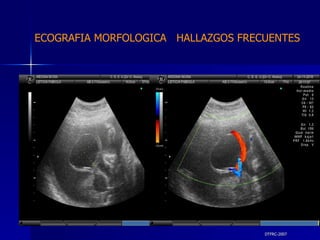

DTFRC-2007 ECOGRAFIA MORFOLOGICA  HALLAZGOS FRECUENTES   GESTACIONES MULTIPLES  N 211 SINDROME TRANSFUCIONAL FETO FETAL (15/20 )

ECOGRAFIA MORFOLOGICA  HALLAZGOS FRECUENTES   CONCLUSION SE OBSERVO UN 14 % DE MALFOMACIONES FETALES  EL SISTEMA NERVIOSO CENTRAL Y EL GENITO URINARIO SON LOS  SISTEMAS MAS AFECTADO CON MALFORMACIONES. ( 46 % ) NO SE OBSERVA DIFERENCIA SIGNIFICATIVAS SEGÚN EL GRUPO  ETARIO. NO SE OBSERVO DIFERENCIA SIGNIFICATIVAS SEGÚN LAS  INDICACIONES PARA LA  REALIZACIÓN DEL ESTUDIO. ( GRUPO BAJO Y ALTO RIEGO )